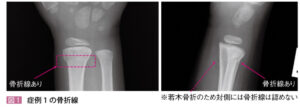

| 病態 | 多くは高齢者の低エネルギー外傷だが、小児や成人でも生じる。小児では転倒などの低エネルギー外傷で生じ、若木骨折となることが多い。成人では交通事故などの高エネルギー外傷で生じ、手術が必要なことも多い。半数以上に尺骨茎状突起骨折の併発を認める。 |

| 検査 | 【身体所見】 手関節発赤腫張、フォーク状変形、橈側の圧痛、回内回外制限 【画像検査】 Xp:手関節2方向で撮像し骨折線を探す、尺骨茎状突起や舟状骨も確認する 小児の場合は若木骨折を疑う(左右確認) 小児で転位が強い場合はSalter-Harris分類を行い手術の可能性があれば即整形コンサルト![]() |

小児の場合は若木骨折を疑う(左右確認)

小児で転位が強い場合はSalter-Harris分類を行い手術の可能性があれば即整形コンサルト